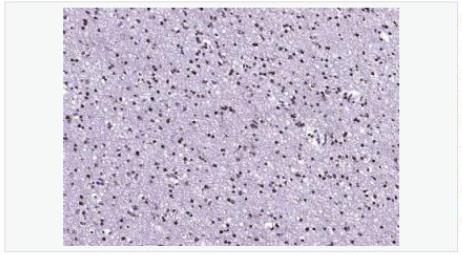

image.png                                                                                                                                                  本产品仅供科研使用。不能用于人和动物治疗等其它临床诊断使用!